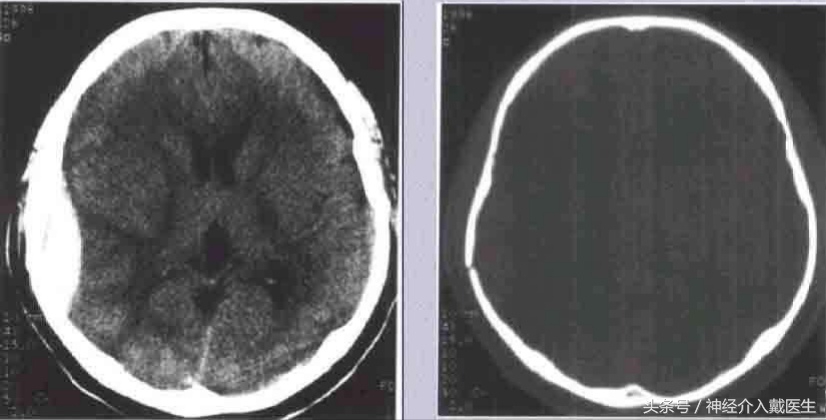

骨折治疗的基本原则是:复位,固定和功能锻炼,颅骨因只起保护大脑作用,然后头颅是球形的,又不需要活动,所以基本符合骨折治疗原则,但是有些骨折对颅脑产生影响,所以治疗上有些与众不同。 通过拍片、CT等检查,发现颅骨骨折了,根据骨折的分类不同处理办法也不一样。

儿童生长性骨折:好发于额顶部,为小儿颅盖线形骨折中的特殊类型,婴幼儿多见。一般认为小儿硬脑膜较薄且与颅骨内板贴附较紧,当颅骨发生骨折裂缝较宽时,硬脑膜亦常同时撕裂、分离,以致局部脑组织、软脑膜及蛛网膜突向骨折的裂隙。由于脑搏动的长期不断冲击,使骨折裂缝逐渐加宽,以致脑组织继续突出,最终形成局部搏动性囊性脑膨出,病儿常伴发癫痛或局限性神经废损。治疗原则以早期手术修补硬脑膜缺损为妥。 凹陷骨折多见于额、顶部,常为接触面较小的钝器打击或头颅碰撞在凸出的物体上所致。着力点头皮往往有擦伤、挫伤或挫裂伤。颅骨大多全层陷入颅内,偶尔仅为内板破裂下凹。一般单纯凹陷骨折,头皮完整,不伴有脑损伤多为闭合性损伤,但粉碎凹陷骨折则常伴有硬脑膜和脑组织损伤,甚至引起颅内出血。

( 1 )闭合性凹陷骨折 儿童较多,尤其是婴幼儿颅骨弹性较好,钝性的致伤物,可引起颅骨凹陷,但头皮完整无损,类似乒乓球样凹陷,亦元明显的骨折线可见。患儿多无神经机能障碍,无需手术治疗。如果凹陷区较大较深,或有脑受压症状和体征时,可于凹陷旁钻孔,小心经硬膜外放入骨撬,将陷入之骨片撬起复位。术后应密切观察以防出血。

成年人单纯凹陷骨折,如果面积大于 5cm,或者直径,深度超过 lcm ,或者伴有神经缺损症状和体征,需要手术治疗。